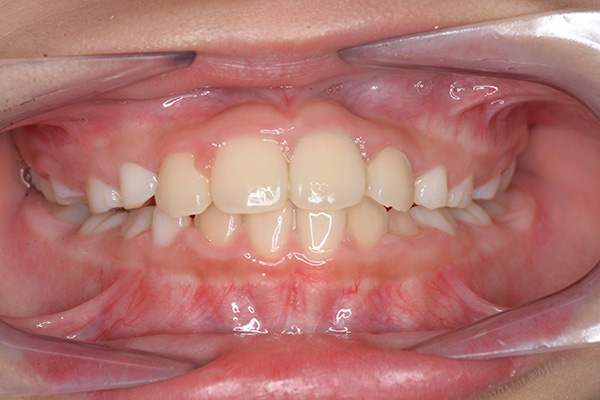

動的治療開始前(9歳7ヵ月)

動的治療開始前

(9歳7ヵ月)

口腔内所見 over jet -2.5mm、over bite 2.0mm、大臼歯関係はⅠ級 。Hellmanのdental ageはⅡCであり前歯部は反対咬合を呈していた。